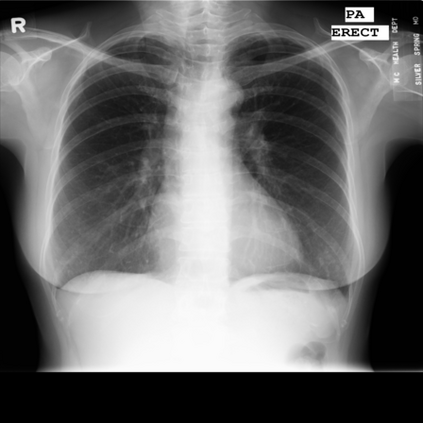

The integration of deep learning systems into healthcare has been hindered by the resource-intensive process of data annotation and the inability of these systems to generalize to different data distributions. Foundation models, which are models pre-trained on large datasets, have emerged as a solution to reduce reliance on annotated data and enhance model generalizability and robustness. DINOv2 is an open-source foundation model pre-trained with self-supervised learning on 142 million curated natural images that exhibits promising capabilities across various vision tasks. Nevertheless, a critical question remains unanswered regarding DINOv2's adaptability to radiological imaging, and whether its features are sufficiently general to benefit radiology image analysis. Therefore, this study comprehensively evaluates DINOv2 for radiology, conducting over 100 experiments across diverse modalities (X-ray, CT, and MRI). To measure the effectiveness and generalizability of DINOv2's feature representations, we analyze the model across medical image analysis tasks including disease classification and organ segmentation on both 2D and 3D images, and under different settings like kNN, few-shot learning, linear-probing, end-to-end fine-tuning, and parameter-efficient fine-tuning. Comparative analyses with established supervised, self-supervised, and weakly-supervised models reveal DINOv2's superior performance and cross-task generalizability. The findings contribute insights to potential avenues for optimizing pre-training strategies for medical imaging and enhancing the broader understanding of DINOv2's role in bridging the gap between natural and radiological image analysis. Our code is available at https://github.com/MohammedSB/DINOv2ForRadiology